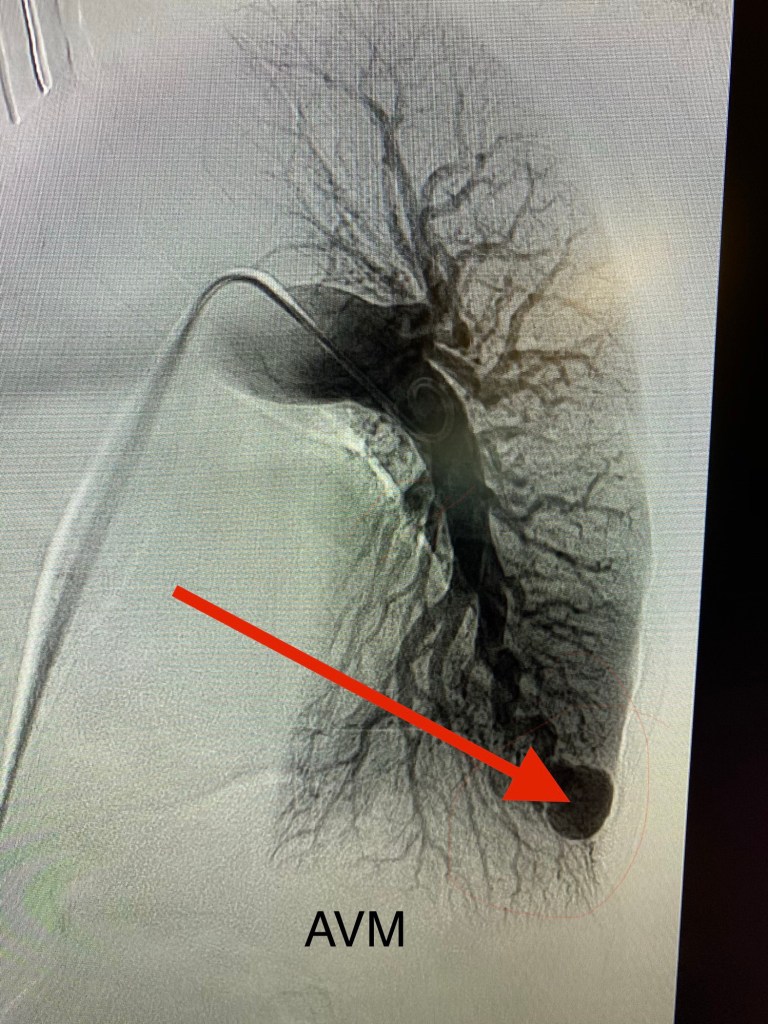

In my last entry, I talked about my embolization procedure. So it’s convenient timing that, last week, I had my follow up imaging to check in on the results of the procedure. It’s an echocardiogram/bubble study. Did I describe this earlier? I’ll run through it again. So, echocardiogram (echo) is an ultrasound image of your heart. The bubble study happens by having an IV placed, and then a Cardiology doc injects agitated saline (so that there are microbubbles) into the vein. On the echo screen, the bubbles can be seen traveling into the right side of the heart. Normally, you would not expect to see bubbles returning to the left side of the heart from the lungs. Last summer, I had a BUNCH of bubbles come back…I remember.

Negative. Not improved, better than before, slightly better….NEGATIVE. As in, someone like my husband with no pulmonary AVMs would have a negative bubble echo and now I do too!!! I knew this was better than what was expected. Furthermore, my follow-up is in FIVE years. I remembered at my initial visit to the HHT center, Dr Hammill talking about “someday” if I’m stable, I “might” be able to space visits out by 5 years, and here I am already. WHAT?!

Speaking of “our” team…here’s the latest on that. I mentioned that all three kids tested positive genetically. Earlier this year they all had clinical testing. All of their brains are clear. But, all of them have pulmonary AVMs like me. All. Of. Them.

OK. So, Maggie has AVMs, but they are all too small to treat. So, she gets observed for any changes. Actually, we will all be observed for the rest of our lives. Treatment is as necessary. Connor and Brady both have AVMs large enough to treat. They’ll both have procedures just like mine. They were scheduled March 19 of this year, which unfortunately was the same week our OR closed to all elective cases due to the COVID-19 outbreak. They’re back on the schedule for August 20, so any and all prayers for their safety and two successful procedures are welcomed. I have ALL the confidence in their care team, as it will be the same as mine was. I’m sure there will be anxiety that day, but truthfully, I’ll be so glad when they’re on the other side of this, and their AVMs are fixed too.